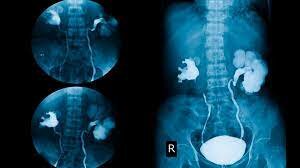

Urografía

Un urograma por tomografía computarizada es un examen por imágenes que se utiliza para evaluar las vías urinarias. Las vías urinarias comprenden los riñones, la vejiga y los conductos (uréteres) que transportan la orina desde los riñones hasta la vejiga.